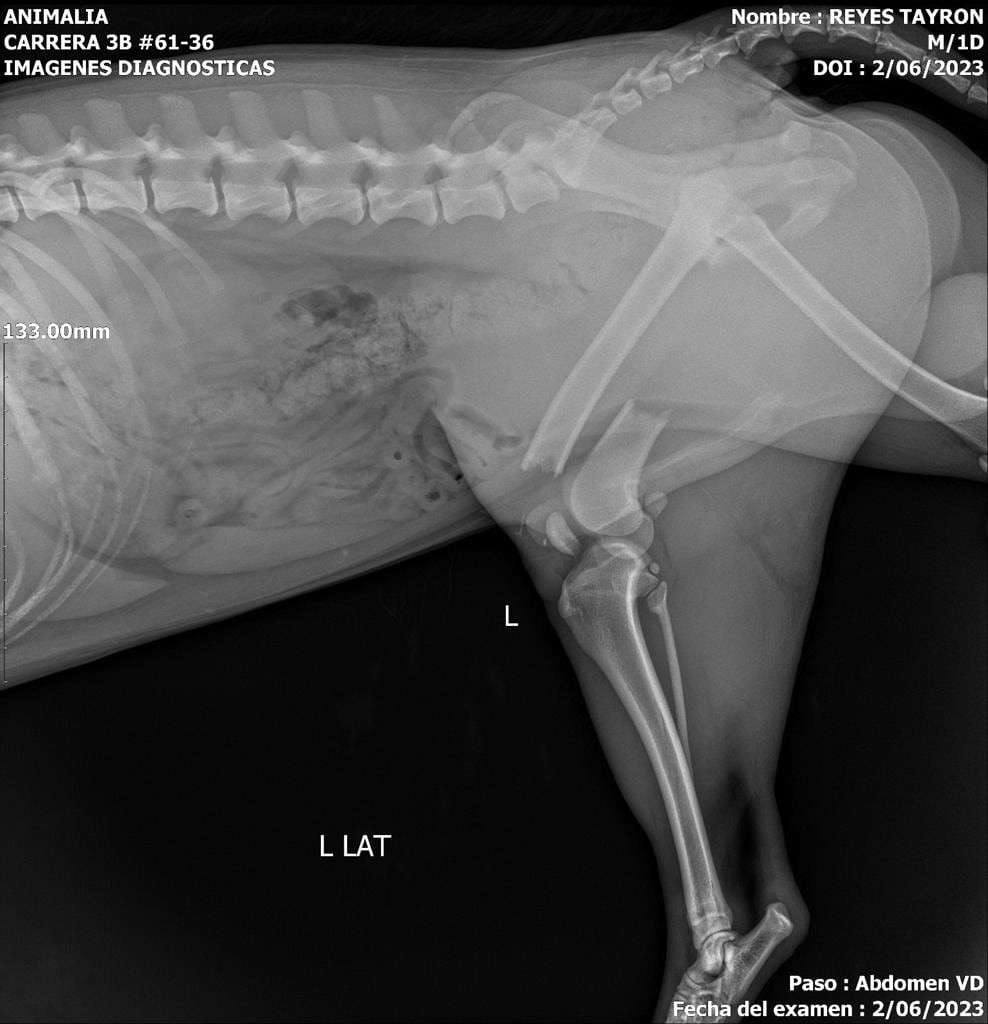

El 2 de julio de 2023, Tayron, un perrito criollo de aproximadamente 2 años, ingresó a una veterinaria en la localidad de Chapinero tras el reporte de su caída de la terraza en un tercer piso, causando la fractura de dos de sus patas.